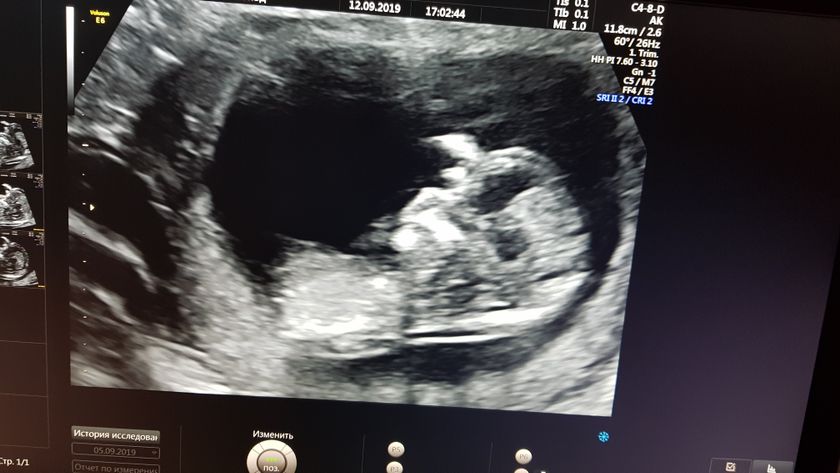

Сходили на узи, все нашли что потеряли неделю назад, вроде все хорошо. Но в заключении написали высокий риск задержки развития, я запереживала, скинула результаты подруге которая занимается скринингами платно, возможно буду переделывать там, пока жду что напишет. ИИИИ ????Похоже у нас снова будет доченька ???. Я счастлива) конечно и мальчику буду рада, но почему то девочка вызывает у меня умиление. С мужем думаем о женском имени, в приоритете Яна и Мия) он за первое я за второе) решим когда родится, если не передумаю ещё 100 раз) Еве тем временем сегодня 7 месяцев, вчера все поздравили, спасибо огромное)???. Естественно весь день провела в ЦпСиР и традиционные ежемесячные фотки не сделала, буду завтра этим заниматься. И для сравнения оба моих ребёнка на примерно одинаковом сроке. Первое фото Евы, второе — малыш в животике. По моему очень похожи))

Здорово, отличные новости, малышата похожи?